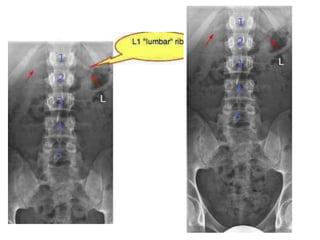

LUMBAR RIB (GORILLA RIB)

• It grows from the costal component of L1

vertebra.

• Its prevalence is much more common

than the cervical rib, but stays

undiagnosed as it normally doesn’t cause

symptoms.

• It might be mistaken with the fracture of

transverse process of L1 vertebra.

LUMBAR RIB (GORILLARIB) • It grows from the costal component of L1 vertebra. • Its prevalence is much more common than the cervical rib, but stays undiagnosed as it normally doesn’t cause symptoms. • It might be mistaken with the fracture of transverse process of L1 vertebra.